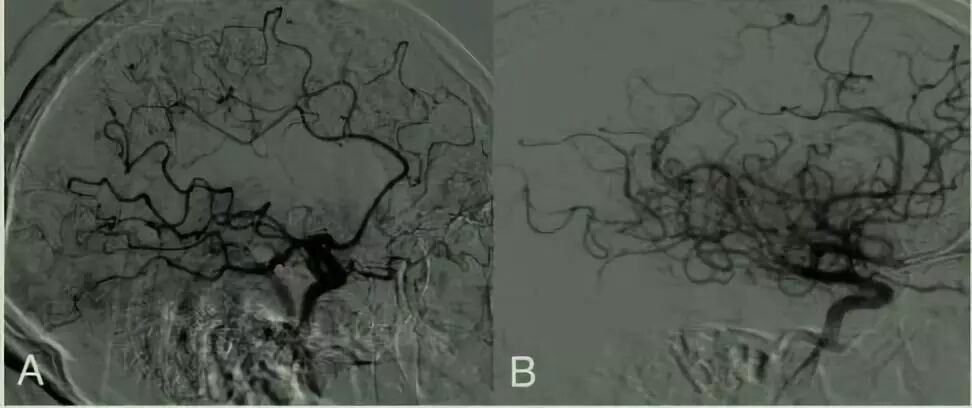

图1 eTICI分型方法

按照该分型方法:eTICI0级是指远端完全无血流;eTICI1级指取出部分血栓但远端仍无血流;eTICI2a级是指远端血流恢复至1%-49%;eTICI2b50是指50-66%的灌注;eTICI2B67是指达到67-89%的血流灌注;eTICI2C是指90-99%的灌注;eTICI3级是指实现100%的灌注。eTICI血流分级准确程度和患者影像资料的丰富程度显著相关,血流分级诊断最困难的是区分eTICI 2b50和eTICI 2b67,eTICI2C和eTICI3级的差异虽然很小,但在区分时达到了很高的一致性。